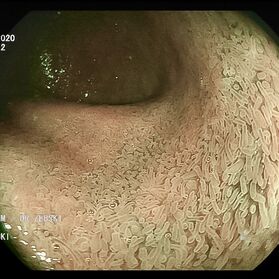

Die Darmspiegelung ist der uneingeschränkte Goldstandard für die Diagnostik und Vorsorge sämtlicher Erkrankungen des Dickdarms und des untersten Dünndarms. Die hochauflösende Bildqualität (High Definition) unserer modernen Videokoloskope ermöglicht eine zuverlässige Einordnung nahezu sämtlicher entzündlicher oder geschwulstiger Veränderungen der Dickdarmschleimhaut.

Die Darmspiegelung hilft, dass Darmkrebs gar nicht erst entstehen kann. Denn während der Untersuchung werden auch Polypen entfernt, aus denen sich der Darmkrebs in der Regel entwickelt. Von allen Maßnahmen zur Früherkennung dieser Polypen besitzt die Koloskopie die höchste Empfindlichkeit. Sie weist kleinste Polypen, aber auch Darmkrebs nach, der noch keinerlei Symptome macht. Die Abtragung dieser Polypen erfolgt direkt, wenn sie entdeckt werden. Das geschieht völlig schmerzfrei. Durch die Abtragung der Polypen kann die Entstehung von Darmkrebs effektiv verhindert und die krebsbedingte Sterblichkeit gesenkt werden.